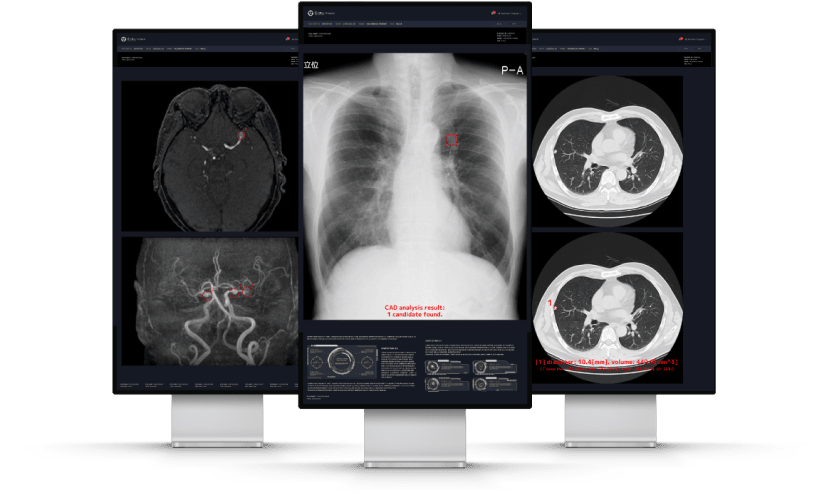

胸部CT画像から肺結節の候補領域を検出

胸部CT画像から肺野領域において、肺結節候補領を自動検出し、その体積と最大径を計測することで、医師の読影診断を支援するソフトウェアです。

胸部X線画像における包括的な

読影支援を提供

胸部X線画像から肺結節・浸潤影・無気肺・間質性陰影候補を検出する機能に加えて、胸腔内の空気含有面積・肋骨横隔膜角・心胸郭比・縦隔幅・大動脈弓径を自動計測する2つのソフトウェアを統合した新たな製品です。

MRA診断を進化させる

脳動脈瘤検出サポートテクノロジー

脳MRA画像から嚢状動脈瘤に類似した領域(2mm以上)を検出することで、医師による読影をサポートします。本ソフトウェアを併用して読影した場合、医師単独での読影感度68.2%は77.2%に大幅に向上しました(放射線科医5年未満:69.6% → 81.2%、放射線科医5年以上:77.2% → 82.0%、脳神経外科医6年未満:53.7% → 62.3%、脳神経外科医6年以上:77.0% → 88.5%)。